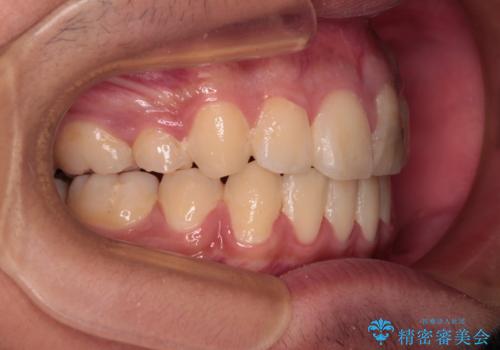

膨らんだ口元 ワイヤー装置での抜歯矯正

- 口元の突出感を気にして来院された患者様です。

上下前歯が著しく前突している状態であったので、上下左右の第1小臼歯4本を抜歯し、ワイヤー装置にて矯正治療を行うこととしました。

小学生の頃に上顎前歯をぶつけ、歯の一部が破損している状態であったので、歯根が歯槽骨と癒着して移動しない可能性がありましたが、無事に治療を終えることができました。

受験勉強と重なり、舌のトレーニングが十分に行えず、高校生としてはやや長期間の治療となりました。